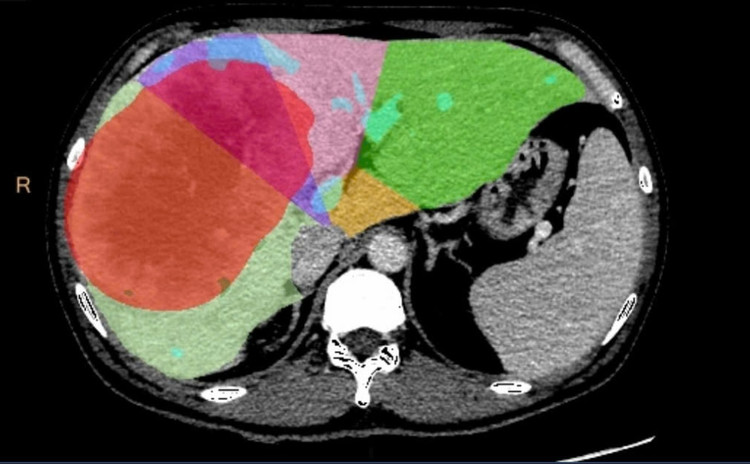

gan-3.jpg

cat-gan-2-dg2-8648.jpg

Khối u gan kích thước lớn, chiếm gần toàn bộ gan bên phải sau khi được cắt bỏ - Ảnh BVCC

Việc triển khai thành công kỹ thuật cắt gan hai giai đoạn tại Bệnh viện Quân y 175 mở ra cơ hội điều trị triệt để, an toàn cho bệnh nhân u gan phát hiện ở giai đoạn muộn, góp phần nâng cao chất lượng điều trị ung thư gan nói chung, căn bệnh đứng đầu về tỷ lệ mắc và tử vong ở nam giới tại Việt Nam, với gần 25.000 ca mắc mới và tử vong mỗi năm.